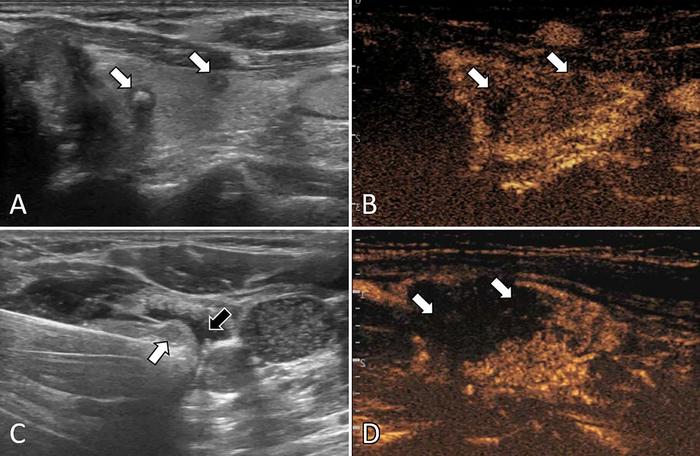

Microwave ablation, a minimally invasive procedure that uses heat to destroy tumors, is currently under preliminary investigation and could be a viable alternative to surgery for some patients.

Researchers looked at 775 patients with ultrasound-detected multifocal Stage I PTC treated with microwave ablation or surgery across 10 centers between May 2015 and December 2021. Propensity score matching—a technique used to compare groups with potentially different baseline characteristics—was performed, followed by comparisons between the two groups. Propensity score matching helps reduce bias by creating comparable groups, allowing for a more reliable assessment of the treatment effect.